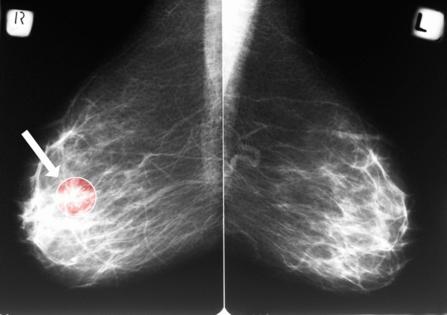

Routine mammograms are best known as a front-line tool for detecting breast cancer. But new research suggests the same X-ray images may also offer an early warning sign for cardiovascular disease — the leading cause of death among women.

A study presented at a Dec. 3 Radiological Society of North America meeting found that calcium deposits visible in the arteries of the breast can help predict a woman's future risk of heart attack, heart failure, stroke and death. The findings add to growing evidence that mammograms may hold untapped value beyond cancer screening.

The condition that mammograms can detect — and act as an early warning of heart problems down the road — is called breast arterial calcification, said Matthew Nudy, an assistant professor of medicine and public health sciences at Penn State College of Medicine who presented the findings.

Breast arterial calcification, or BAC, is relatively common, appearing in an estimated 15% to 25% of screening mammograms. Yet it is not routinely reported.

Despite often being discernible on routine mammograms, radiologists do not typically report the presence of these calcifications "because there's no known association between this breast arterial calcification and breast cancer," Nudy said.